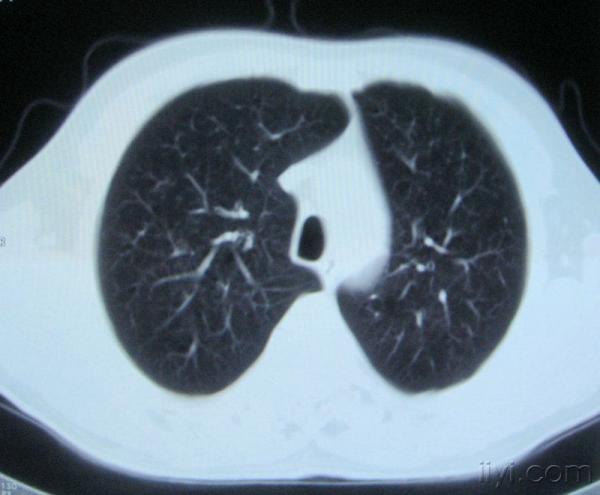

男。60岁,胸片示支气管炎治疗后复查CT。

你指那个肯定是淋巴结,中央系坏死,这很常见,特别在双侧腹股沟会经常看到。这个双侧腋窝及纵隔见多发小淋巴结征。